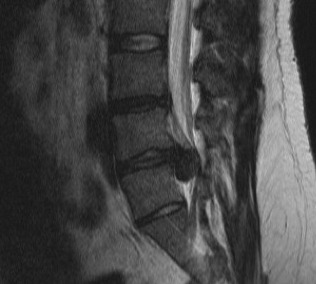

MRI

T2 Sagittal - myelogram

T1 Axial - see nerve root against white fat

Investigation

- gadolinium MRI

- scar enhances but recurrent HNP does not